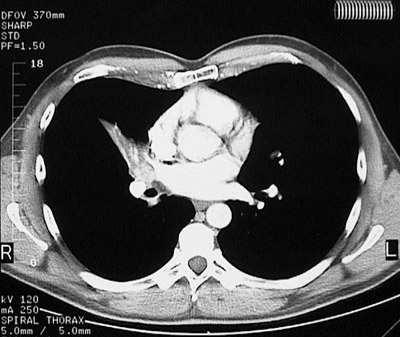

Image 5.1

This chest CT scan with "soft tissue" window demonstrates a

small tumor

that is causing obstruction with atelectasis of the

right middle lobe

.